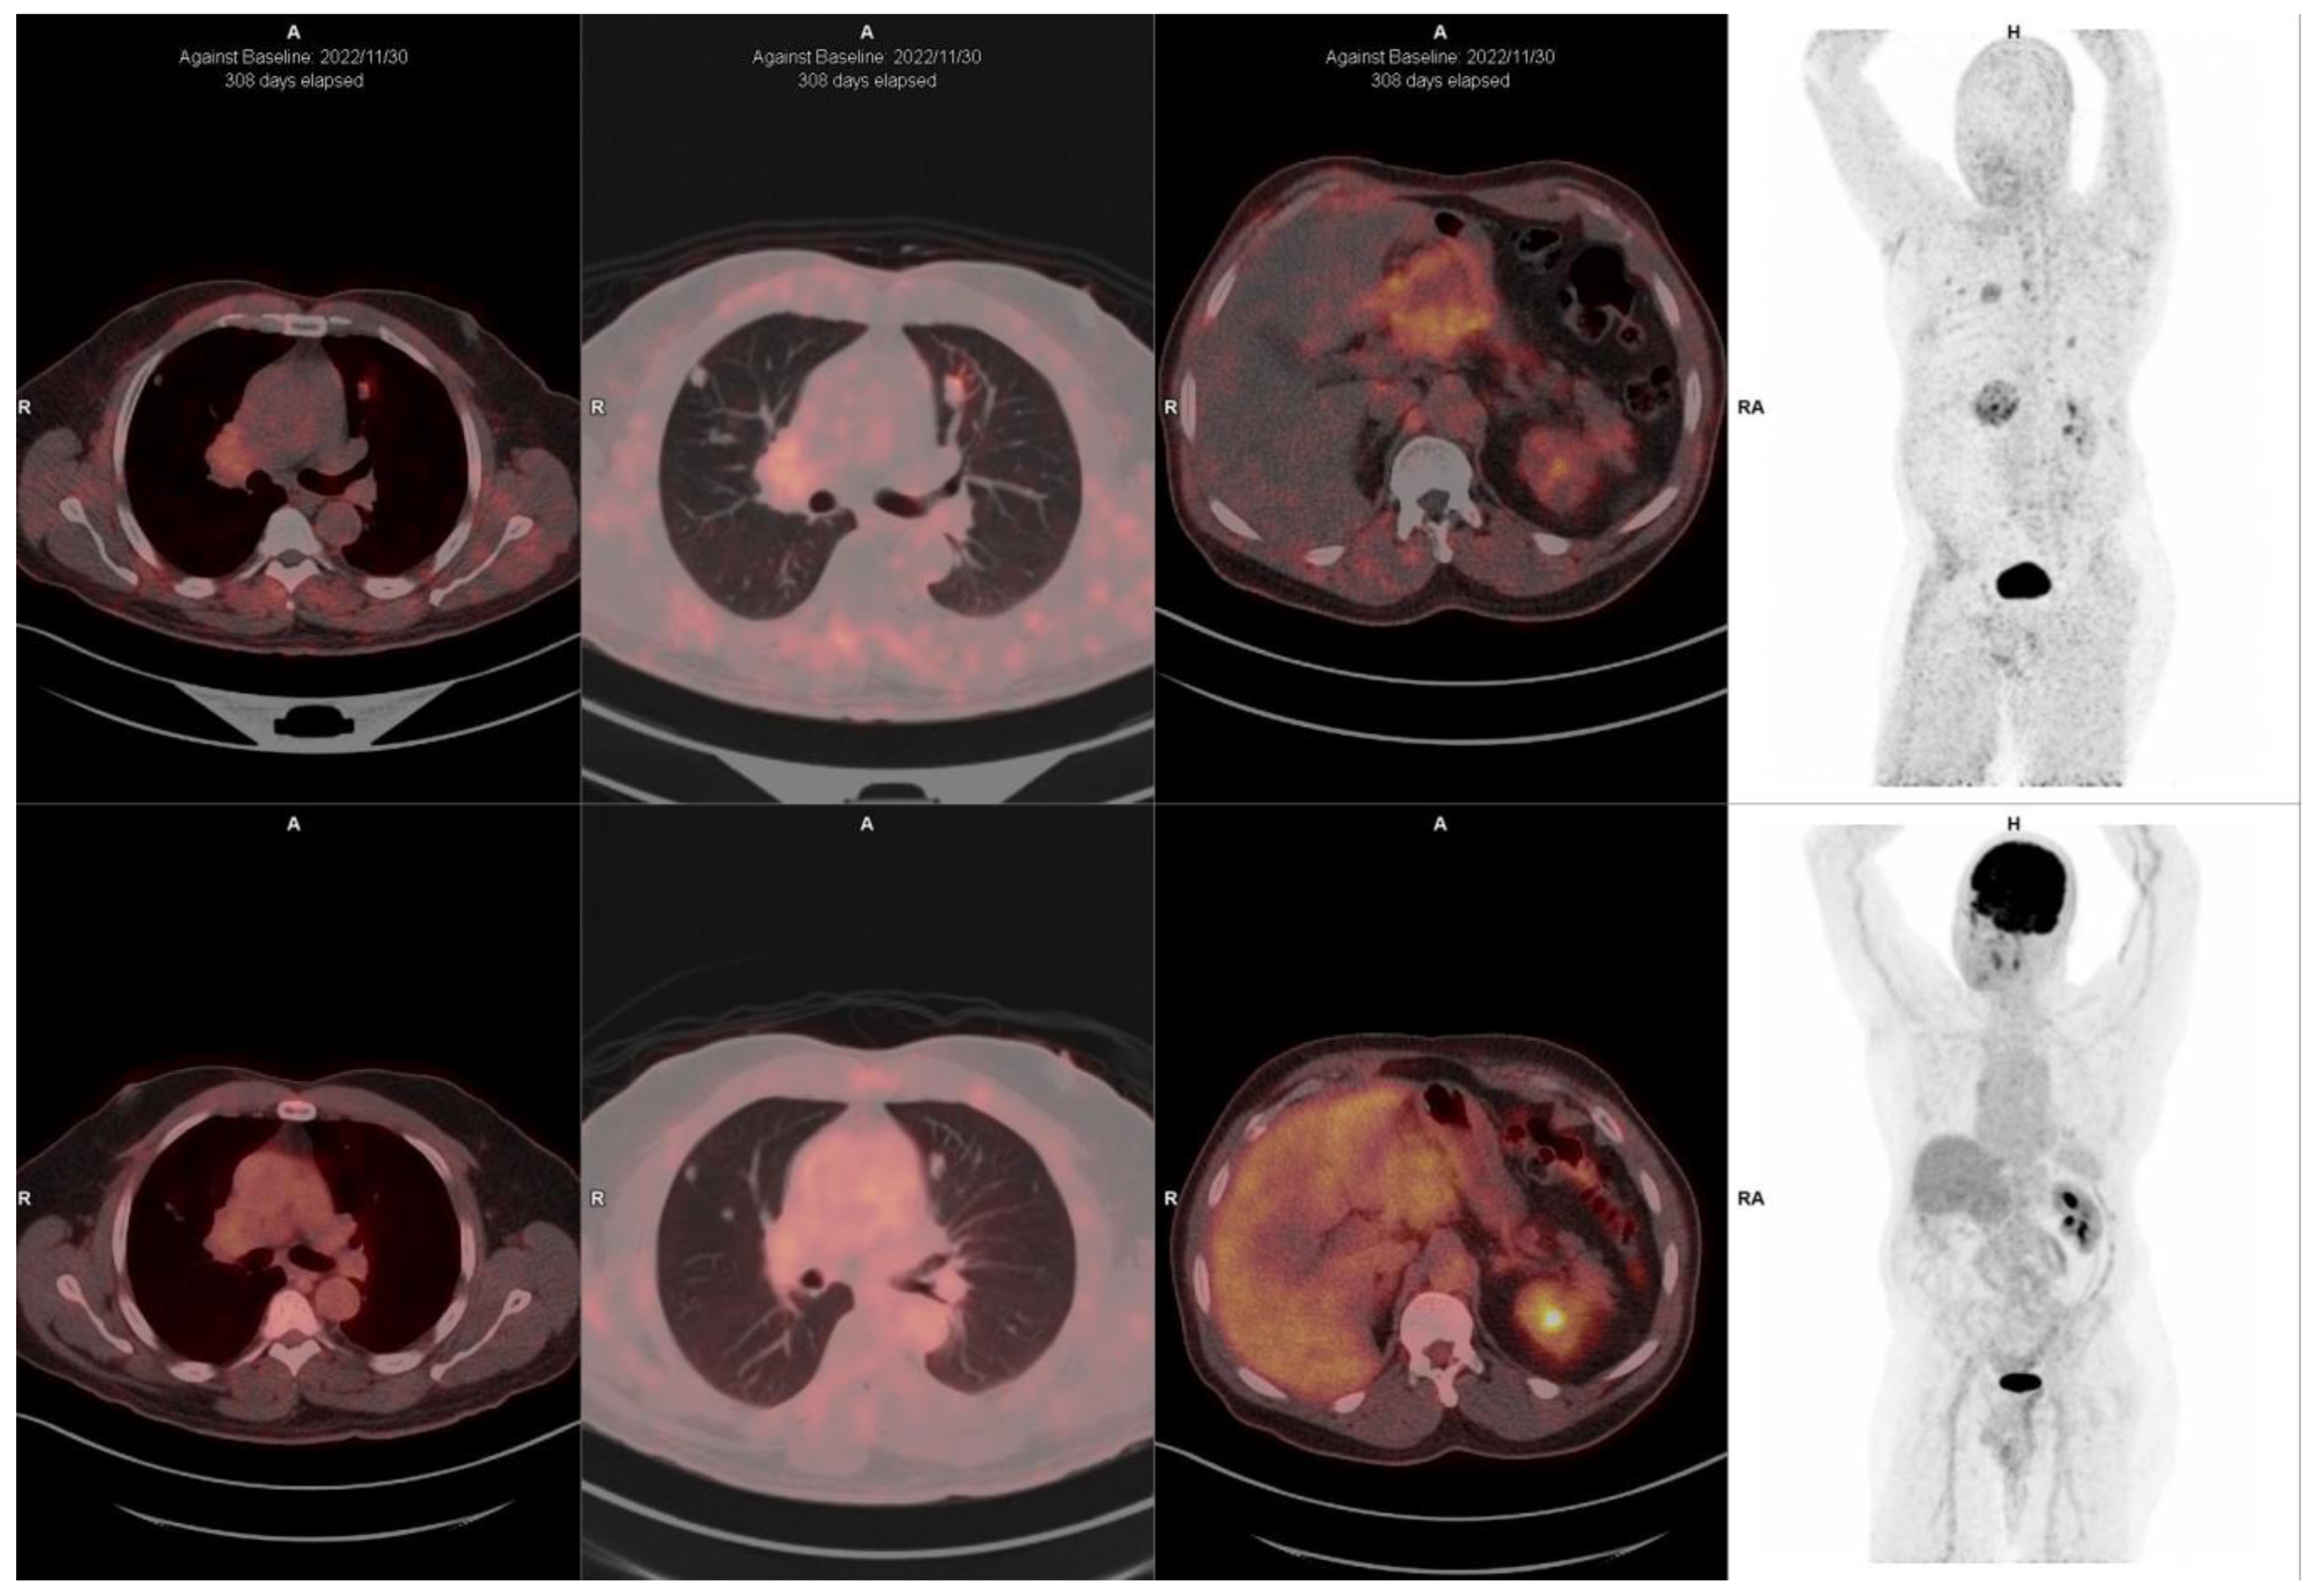

FAPI-Based Radioligands

10. FAPI-Based Theranostic Approaches

12. The Potential Role of FAPI PET-Based Theranostic Approaches